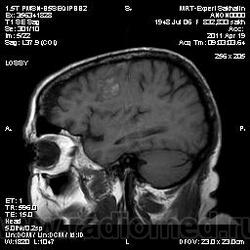

склоняюсь к кровизлиянию в левой теменной долей, начало перехода острой стадии в раннюю подострую( по периферии определяется повышение МРС по Т1 ВИ -метгемоглобин). Справа -старые кортикальные постишемческие глиозно-атрофические изменения. Контрастируется , вероятно за счет формирования участков ангионеогенза.

Уважаемые коллеги-спасибо за высказанные мнения!Женщина 1948 года рождения.Жалобы на головную боль.Динамику мне бы тоже хотелось посмотреть, но не знаю-проходила ли она еще раз у нам исследование.Если да, то обязательно представлю.

О.С., я согласен, что контрастирование нехарактерно для ОНМК, ведь в подострую стадию инфаркта наблюдается, как правило, гиральный тип усиления. Плюс, на ОНМК непохоже то, что поражено почти только белое вещество, а кора интактна. И потом, при такой локализации инфаркта обязательно должна быть яркая клиника, и уж никак не только "головная боль".

Скажите пожалуйста, а что с лобными полюсами полушарий?

Что касается лобных долей мне не хватает мр- изображения . Ну думаю это может быть связано с гиперостозом костей. Для уточнения можно назначить МСКТ.

Ребята, если это ОНМК, то "головной болью" тут никак не обойтись. С таким инсультом быстренько попадают в неврологию.